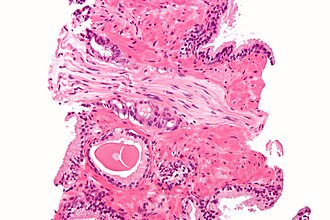

Perineural invasion in prostate carcinoma. H&E stain.

Perineural invasion, also known as perineural tumour, is the presence of a tumour within the nerve sheath. It is abbreviated as PNI.

Generally, it is an indicator of a poor prognosis.

• Tumour within the nerve sheath.